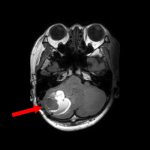

618

'25年4月

40代

小脳血管芽腫

頭蓋内腫瘍摘出術